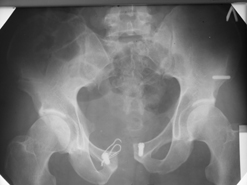

Диагноз : Сочетанная травма. ЗЧМТ. Перелом свода черепа. Ушиб головного мозга.Разрыв лонного и крестцово-подвздошного сочленений с нарушением целостности тазового кольца, с массивной забрюшинной гематомой и пропотеванием в брюшную полость. Перелом 10 ребра справа, осложненный гемопневмотораксом справа, правосторонней пневмонией на фоне ушиба правого легкого. Шок 3-4 ст. Больной поступил в отделение 07.03.2005г. в 16.00 в экстренном порядке через 30 минут после автодорожной травмы.Доставлен КСП. При поступлении состояние больного крайне тяжелое, явления травматического шока, А/Д-80/60 мм.рт. ст. ЧСС-120.В экстренном порядке поднят в операционную, интубирован, совместно с диагностическими мероприятиями лечение шока.При осмотре выявлены перелом 10 ребра справа, разрыв лонного и правого крестцово-подвздошного сочленений. Имеется линейный перелом теменной и височной костей слева с переходом на основание. Диагностическая лапароскопия 07.03.2005г. в 16.30-массивная забрюшинная гематома малого таза.Оставлена контрольная, дренажная трубка.Учитывая кровь в моче произведена цистография - данных за разрыв мочевого пузыря не найдено. Больной переведен в реанимационное отделение.За 08.03.2005г. из брюшной полости выделилось до 1500,0 мл, крови, часть крови реинфузирована. 08.03. в 06.30 наложен торокоцентез справа,удалено 100,0 мл. крови и 200,0 мл. воздуха .. Учитывая продолжающеееся кровотечение в брюшную полость из перелома костей таза, для исключения возможного разрыва внутренних органов 09.03.2005г. произведена Видеолапароскопия., на которой повреждения органов брюшной полости не выявлено.Одновременно произведен шов лонного сочленения проволокой и винтами, с одномоментным наложением стержневого аппарата на кости таза, с целью уменьшения кровотечения из разрывов тазовых сочленений, дренирование гематом. В последующем состояние больного оставалось тяжелым. 10.03.наложена нижняя трахеостома.Далее неоднократно производилась лечебно-диагностическая ФБС.С 10.03 выявлена правосторонняя плевропневмония. КТ головного мозга от 10.03-субарахноидальноекровоизлияние.Срединные структуры не смещены. КТ-контроль от 15.03-открытая моновентрикулярная гидроцефалия4 желудочка. Полисинусит. Постепенно состояние больного медленно прогрессировало к улучшению.С 24.03 переведен на самостоятельное дыхание, а 09.03 переведен в травматологическое отделение.Аппарат стержневой снят из-за перелома стержня (раскрутил больной самостоятельно).После госпитализации в наше отделение проведено дополнительное обследование Рентгекнография, КТ.Хотелось бы услышать Ваше мнение о дальнейшей тактике.-- С уважением, Leonid

Углядел билатеральное повреждение таза. Имеется вертикальная нестабильность со стороны перелома боковой массы крестца, ротационная с контрлатеральной стороны - чрезподвздошный разрыв кп сочленения. Разрыв лона, запирательные отверстия вроде целы.

DS. на сегодняшний день: Вертикальная двусторонняя нестабильная деформация таза, неправильно срастающийся перелом боковой массы крестца слева, срастающийся перелом крыла правой подвздошной кости, застарелый частичный разрыв правого кп сочленения, застарелый разрыв лонного сочленения.

План жизни - оперативное лечение. ЧКО таза (кольцевая опора), последовательная фиксация задних отделов с низведением перелома крестца, синтез лона пластинами, илиосакральное блокирование.

Следует заметить, что подобное привинчивание проволокой лонных костей редко приносит удовлетворение и то только при ротационно-нестабильных повреждениях от бовового сжатия без "ручки корзины". Разрушение заднего комплекса делает неэффективным любую фиксацию передних отделов. Надо обезательно хватать задние отделы.

Нужно выполнить реостеосинтез симфиза пластиной (стабильный остеосинтез

пластиной винтов на 6). Странно, почему этого не сделали сразу, раз уж

вмешались открыто.